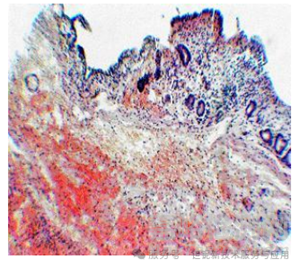

犬膽道造影中,30% 稀土TaO?可清晰顯示直徑≥7 mm 的結(jié)石,肝內(nèi)膽管分支顯影分辨率達(dá) 0.5 mm(圖 9)。相比之下,泛影葡胺組黏膜出現(xiàn)大面積壞死,而 稀土TaO?組僅見輕度淋巴細(xì)胞浸潤(圖 10、圖 11)。

圖10.犬膽囊注射LOT 30 %凝膠混懸液后,蘇木精和伊紅染色,100倍放大。

長期毒性實(shí)驗(yàn)(28天)未見肝腎功能異常,組織切片顯示注射部位僅有少量巨噬細(xì)胞浸潤,證實(shí)生物相容性優(yōu)異。